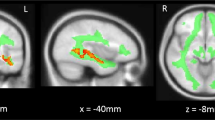

Based on the interaction between diagnosis and cytokine group in relation to verbal fluency, Broca’s area, POp and pars triangularis, and Wernicke’s area, SMG, along with their right hemisphere analogs were selected as regions of interest. Broca’s area volume (left POp, see Supplementary Figure 1) was significantly different between schizophrenia and control groups and this region also showed a significant difference between the schizophrenia elevated and low-cytokine groups (diagnosis: F(1,69)=7.10, P<0.01, cytokine group: F(1,69), 4.17, P<0.05, Figure 4a, Supplementary Table 3). Within the group of people with schizophrenia, the volume of the left POp was decreased by 17% in the high cytokine group compared with the low-cytokine patient group (F(1,29)=9.40, P=0.005, Figure 4a). The volume of Broca’s area was decreased by 20% in the subgroup of individuals with schizophrenia and elevated cytokines compared with the combined mean volume of elevated and low-cytokine controls. There were no significant differences observed in the left or right pars triangularis, right Pop or the left SMG. Although there were no main effects of diagnosis or cytokine group on the right SMG, there was a significant interaction between diagnosis and cytokine group (F(1,69)=5.03, P<0.05). Post hoc tests showed that in patients with schizophrenia, higher cytokines were associated with a 15% smaller right SMG volume (F(1,29)=6.53, P=0.02, Figure 4a), whereas there was no effect of cytokine grouping in controls. For additional MRI results, refer to Supplementary Tables 3 and 4.

Language-related brain areas influenced by elevated cytokine levels in schizophrenia. Significant volumetric changes in areas associated with verbal fluency were found in the left hemisphere (a). The pars opercularis, part of Broca’s area, showed significantly diminished volume in individuals with schizophrenia compared with controls (upper brackets). There was also a significantly decreased average brain volume in the elevated cytokine schizophrenia group as compared with the low-cytokine group in this brain area (lower brackets). The supramarginal gyrus in the right hemisphere showed a significant interaction effect between diagnosis and cytokine group, but there were no significant differences between diagnostic group or cytokine group. Error bars indicate calculated standard error (*P<0.05, **P<0.01). Increases in IL-1β mRNA in schizophrenia are a significant predictor of poorer COWAT scores (b). Similarly, increases in IL-1β mRNA also predict decreased volumes of the left hemisphere pars opercularis in schizophrenia (c). Individuals in the elevated cytokine group are represented by dark red points and those in the low-cytokine group indicated by lighter red points.